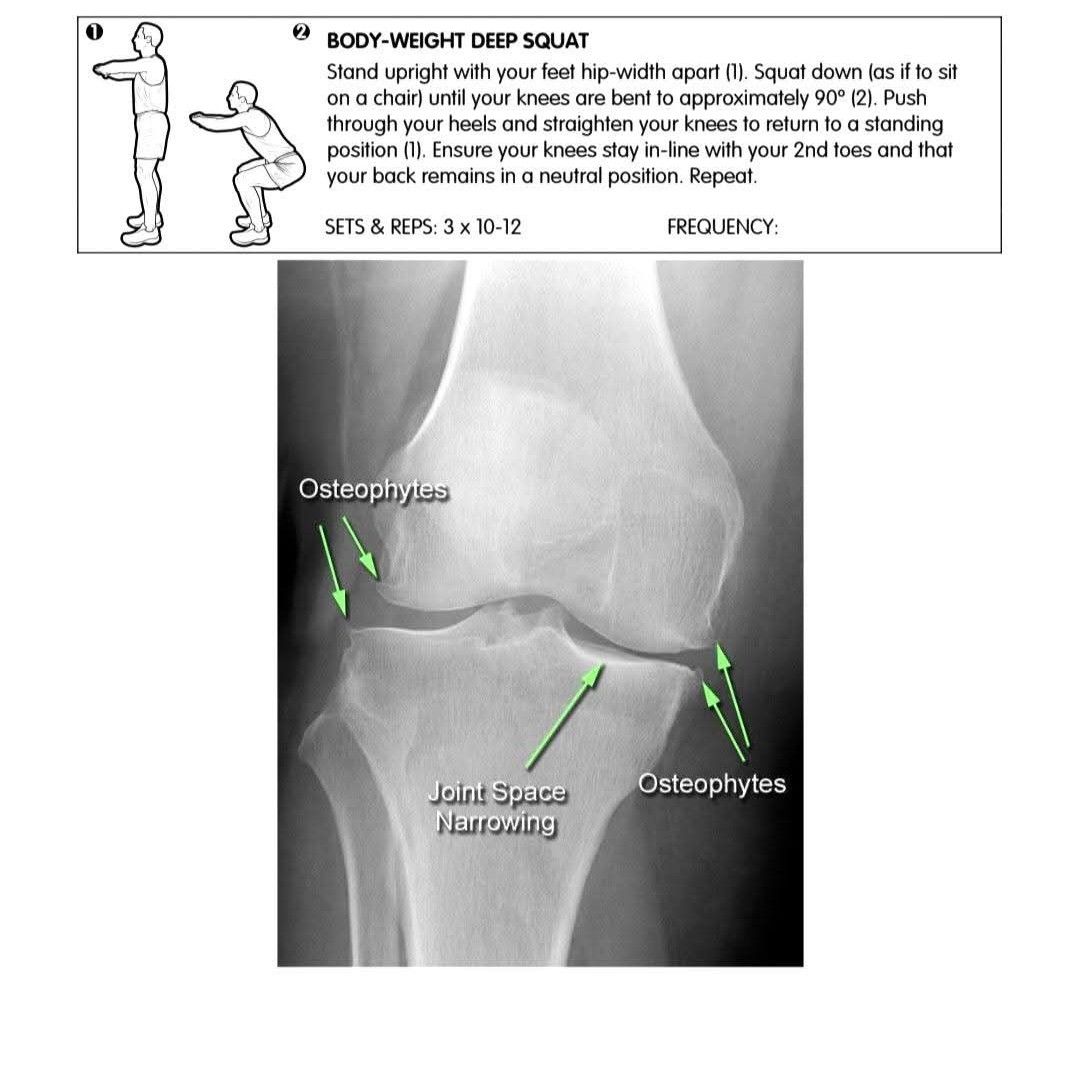

Knee Osteoarthritis Treatment at Sunshine clinic